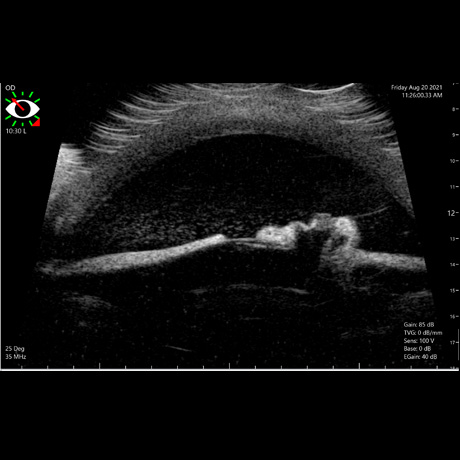

Na Oftalvet dispomos de equipamento avançado, de última geração, que permitem o diagnóstico das mais variadas doenças que afectam o globo ocular e seus anexos.

Nas patologias oftálmicas, o intervalo de tempo decorrido entre o inicio dos sintomas e a implementação do tratamento médico ou cirurgico, é fundamental para um desfecho de sucesso.